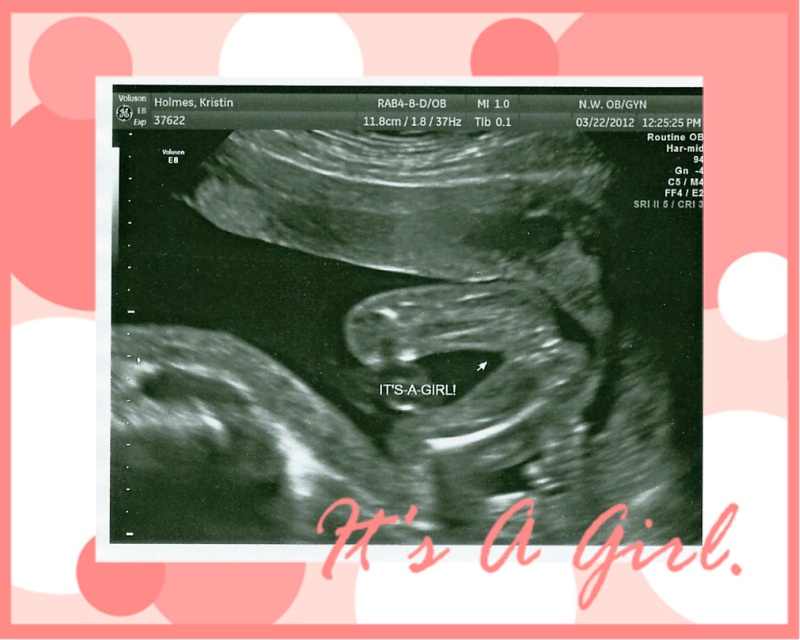

I did ask if there is a nursery, colors, etc. and due to some space issues, Baby girl will be in with atomic and DH for now. They have had a trying year and anything that you all feel like doing would be lovely.

When she emailed me to tell me that she was pregnant with a girl, I knew why I had held onto my girl clothes for so long. Some things are just meant to be!